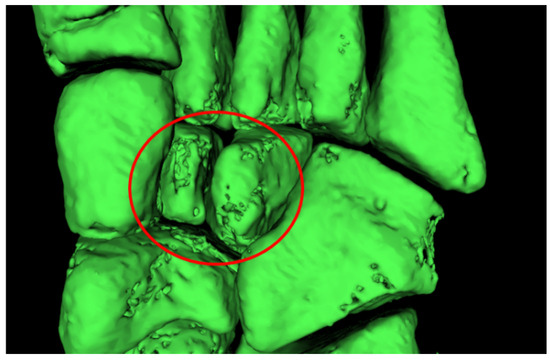

3.1. Imaging Acquisition and Mesh Processing